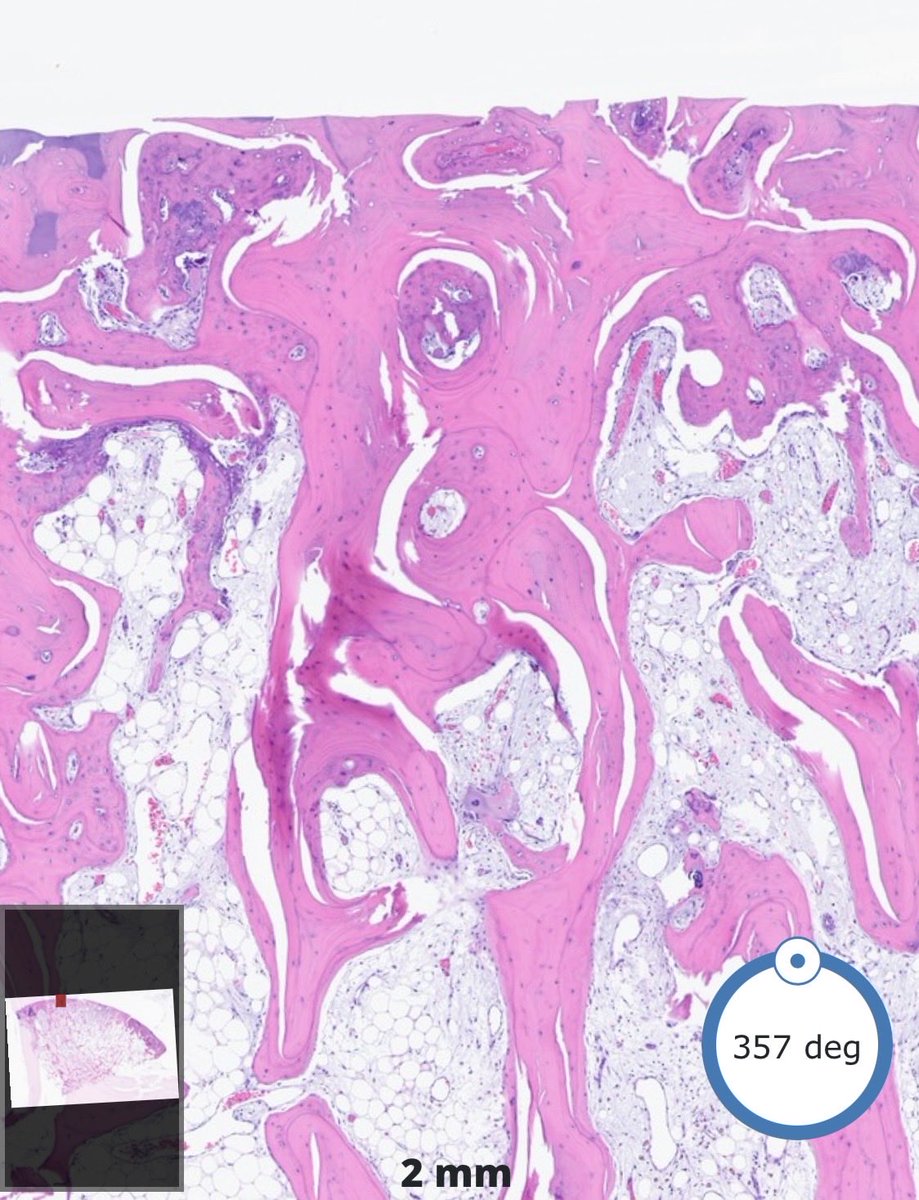

Sclerosed Intraductal Papilloma 🫚🔬 A papilloma with densely fibrotic, hyalinized stroma and compressed fibrovascular cores, often attenuating the epithelial and myoepithelial layers and simulating invasive carcinoma. #PathX #PathTwitter #breastpath

RazaHoda's tweet image. Sclerosed Intraductal Papilloma 🫚🔬

A papilloma with densely fibrotic, hyalinized stroma and compressed fibrovascular cores, often attenuating the epithelial and myoepithelial layers and simulating invasive carcinoma.